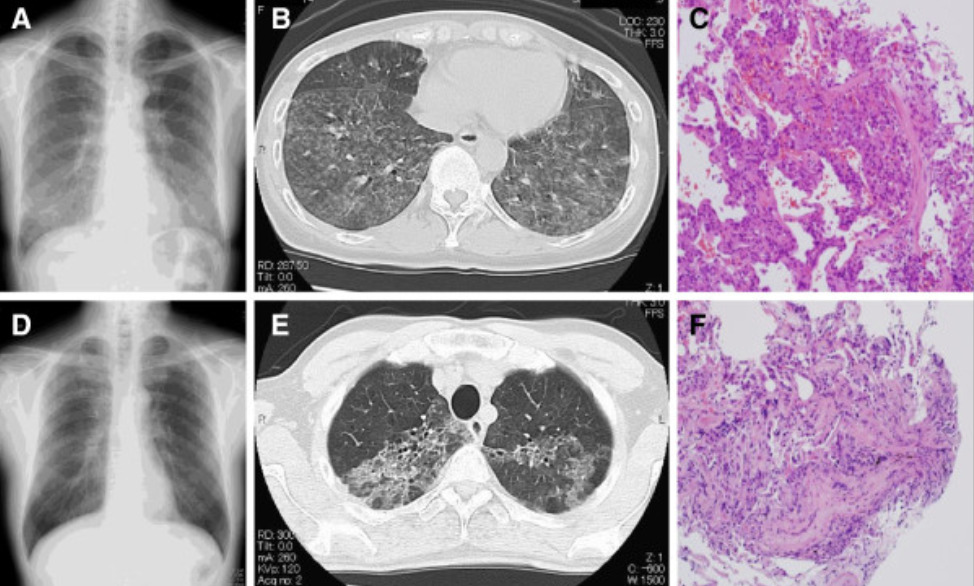

hypersensitivity pneumonitis

hypersensitvity pneumonitis - cause, features, dx, tx

inhalation of env/occupational antigens, usually animal (birds), fungi, bacteria, or inorganic chemicals leading to interstitual lung disease

acute - constitutional, flu-like sx, leukocytosisl; or more chronic - cough, dyspnea, fatigue, weight loss

diagnosed via hx & ct of chest showing fibrosis. also lymphocytosis on bronchoaleolar lavage, noncaseating granulomas on histopathology

avoid antigen, usually resolves spontaneously. can give glucocorticoids if symptoms persist. if refractory, may eventually require lung transplant